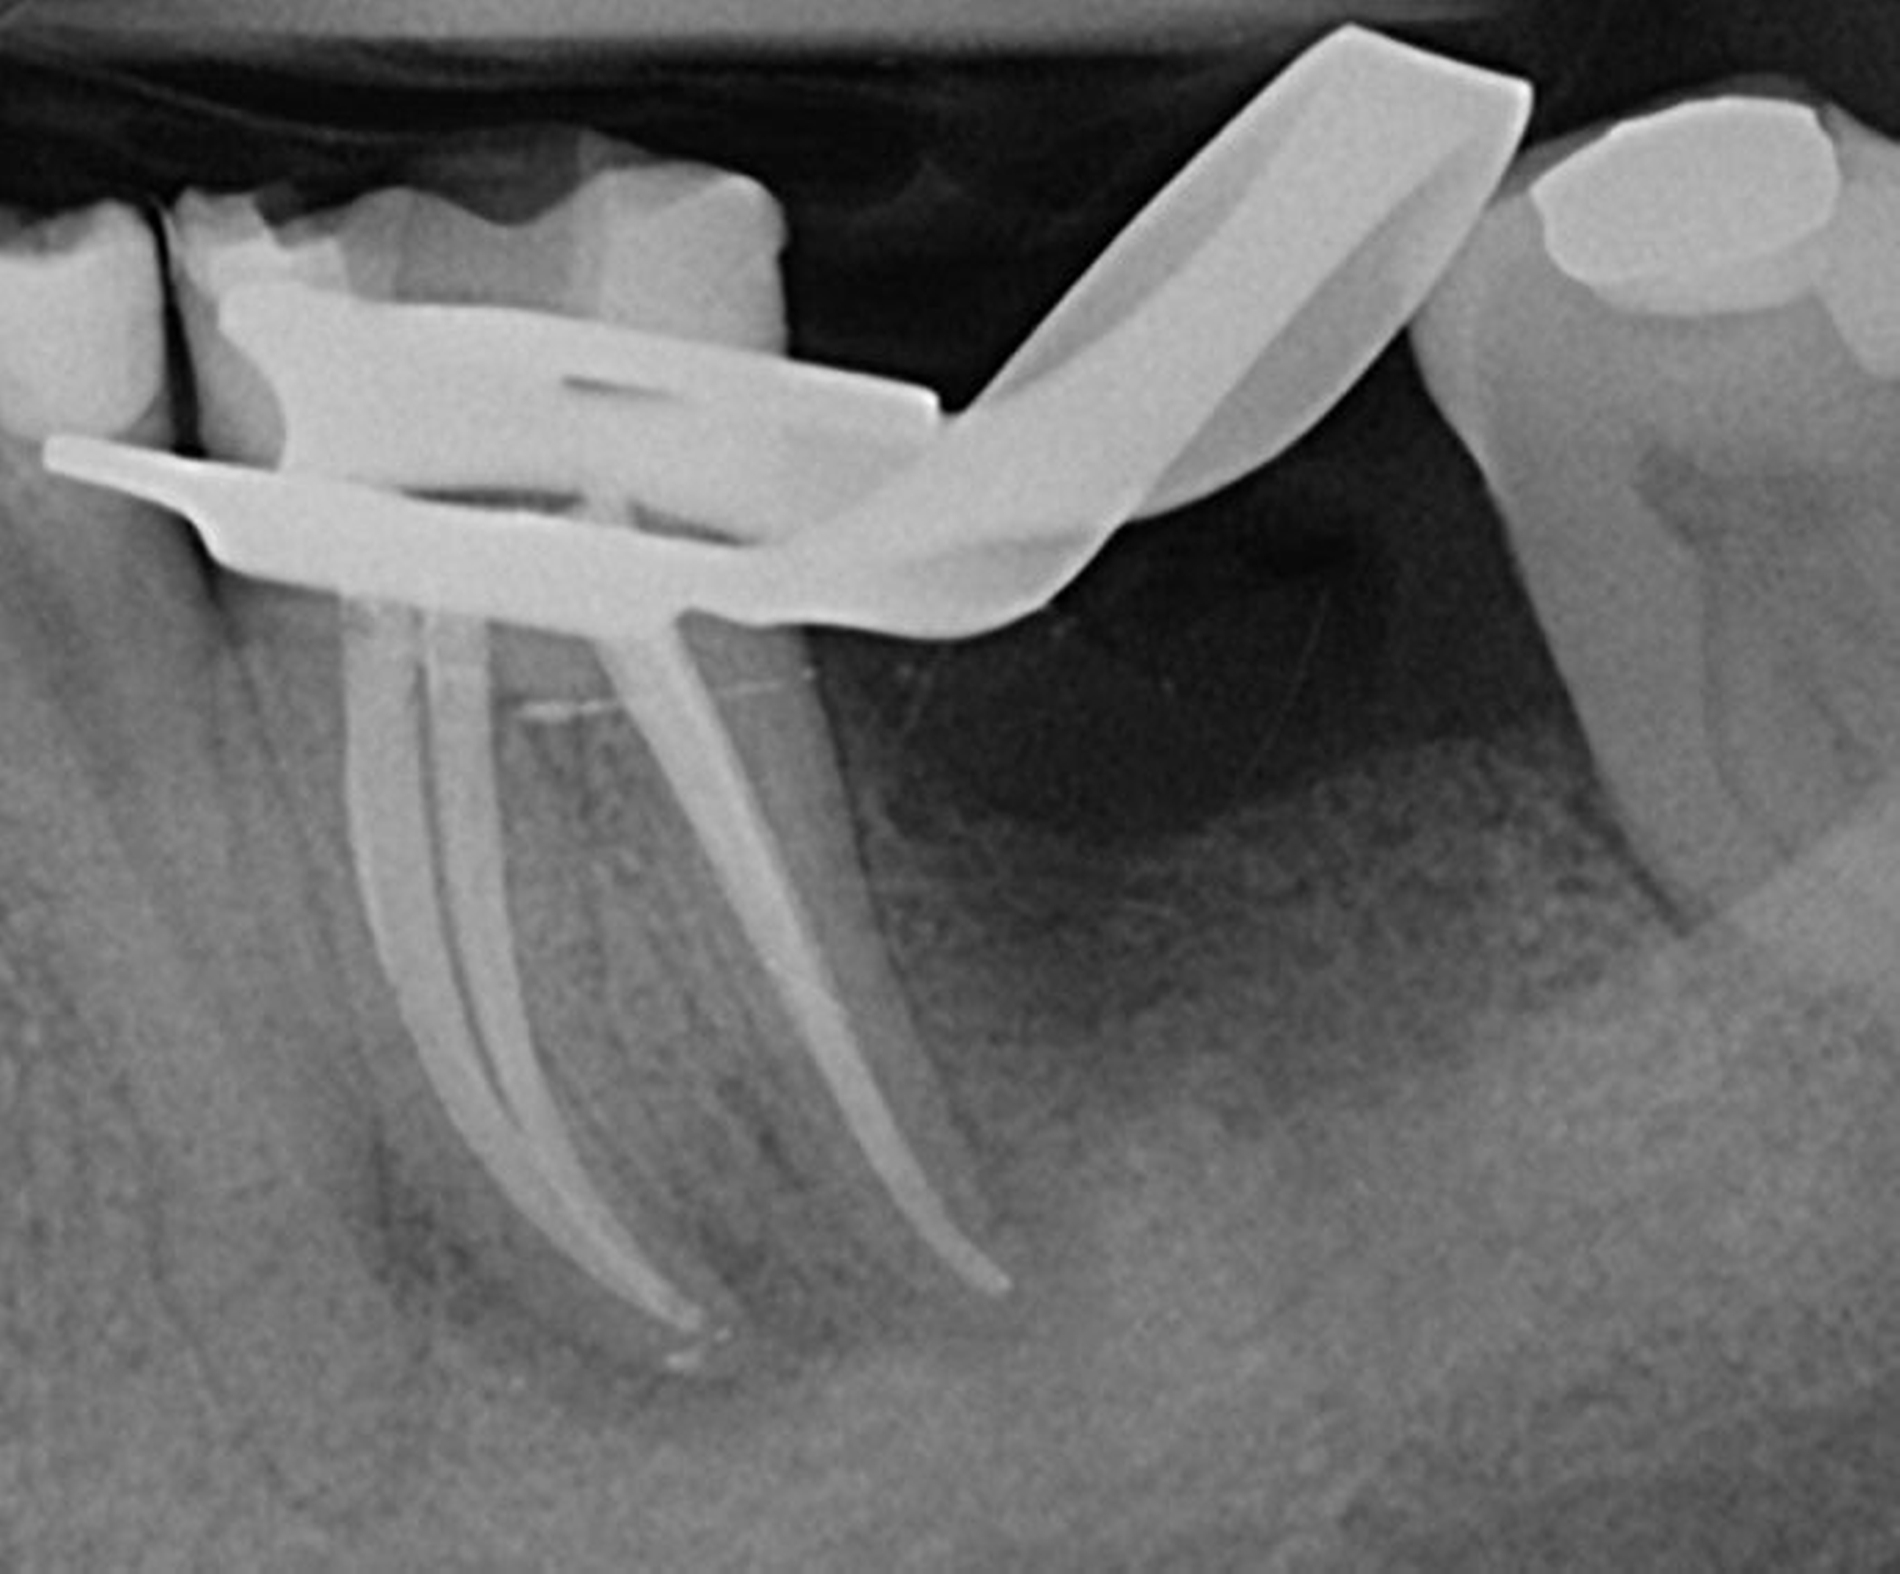

Die Wurzelkanalbehandlungen der Preisträgerer wurden als exzellent eingestuft, da sie einen besonders hohen Schwierigkeitsgrad aufwiesen. Dazu gehören schwierige Ausgangssituationen, etwa bei Durchführung einer Wurzelkanalrevision, bei der eine bereits vorhandene Wurzelkanalbehandlung revidiert werden muss. Auch anatomische Besonderheiten, wie zwei Wurzelkanäle in einer Wurzel, stellen eine besondere Herausforderung dar und bedürfen einer besonders aufwendigen Behandlung.